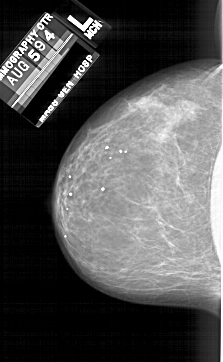

A_1689_1.LEFT_CC

LEFT_CC LINES 5791 PIXELS_PER_LINE 3556 BITS_PER_PIXEL 12 RESOLUTION 43.5 NON_OVERLAY

FILE: A_1689_1.RIGHT_CC.OVERLAY

TOTAL_ABNORMALITIES 1

ABNORMALITY 1

LESION_TYPE MASS SHAPE OVAL MARGINS CIRCUMSCRIBED

ASSESSMENT 4

SUBTLETY 3

PATHOLOGY BENIGN

TOTAL_OUTLINES 1

BOUNDARY